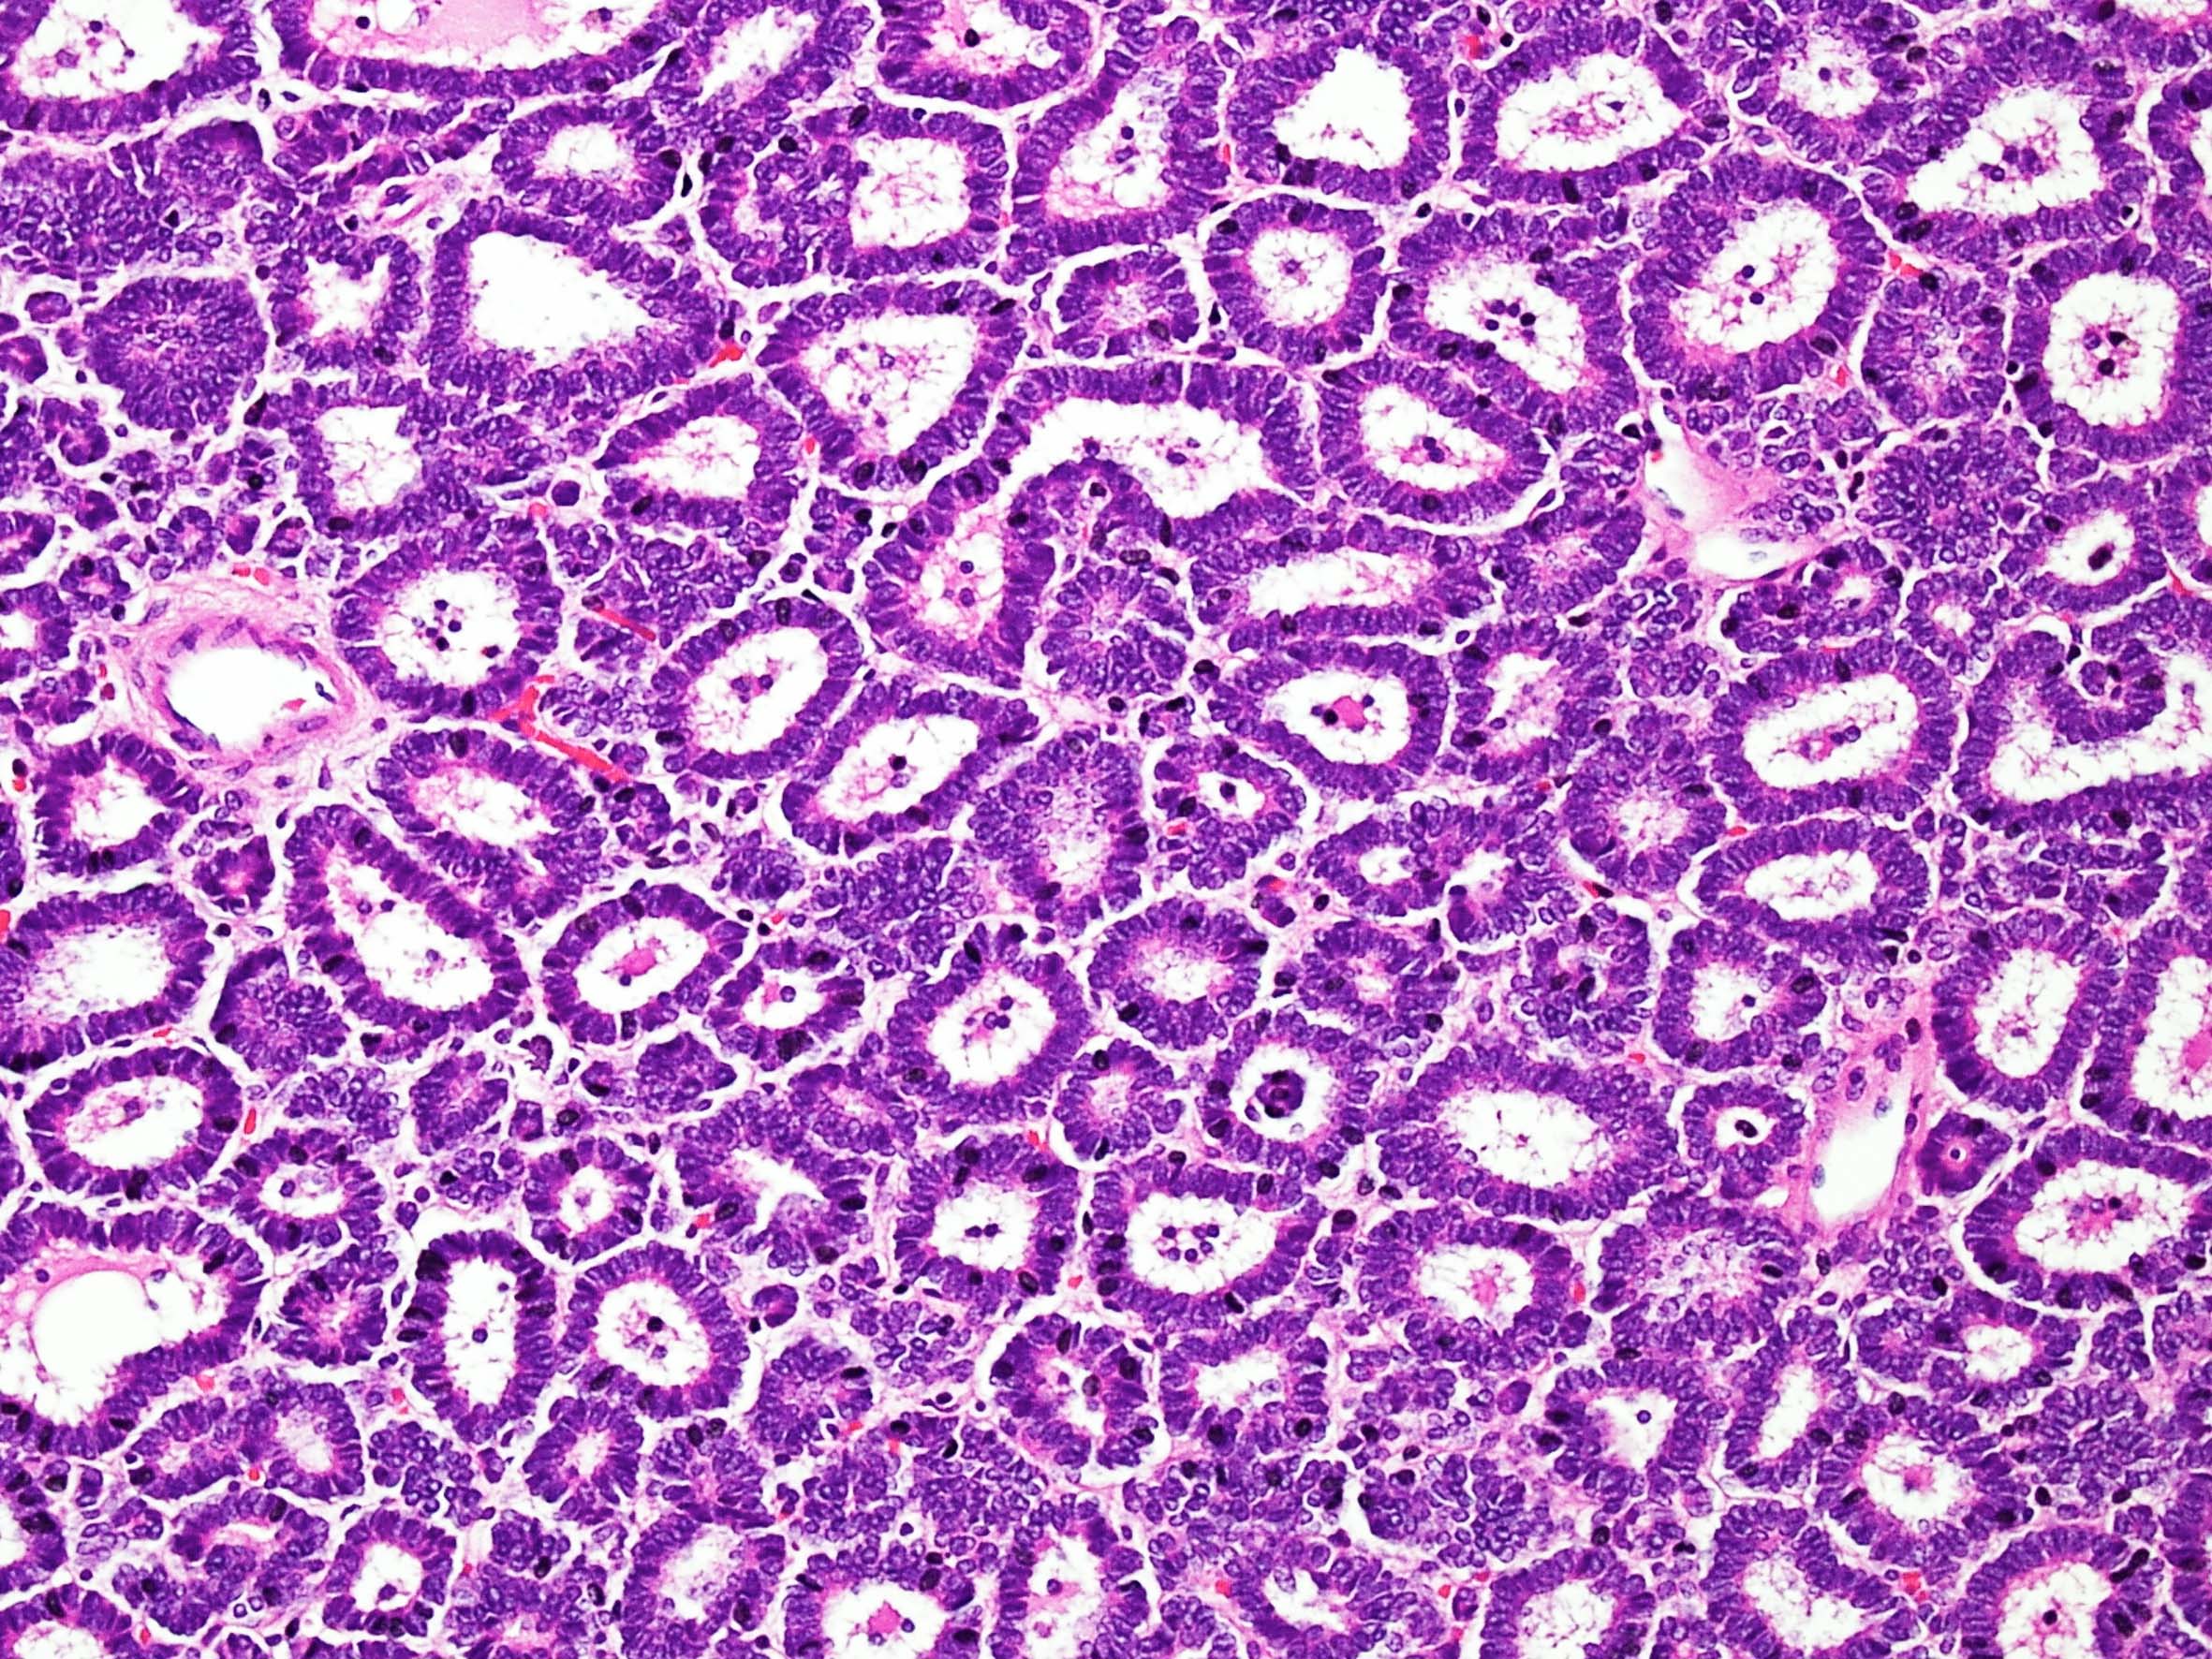

Case description (by case creator):

Metanephric adenoma